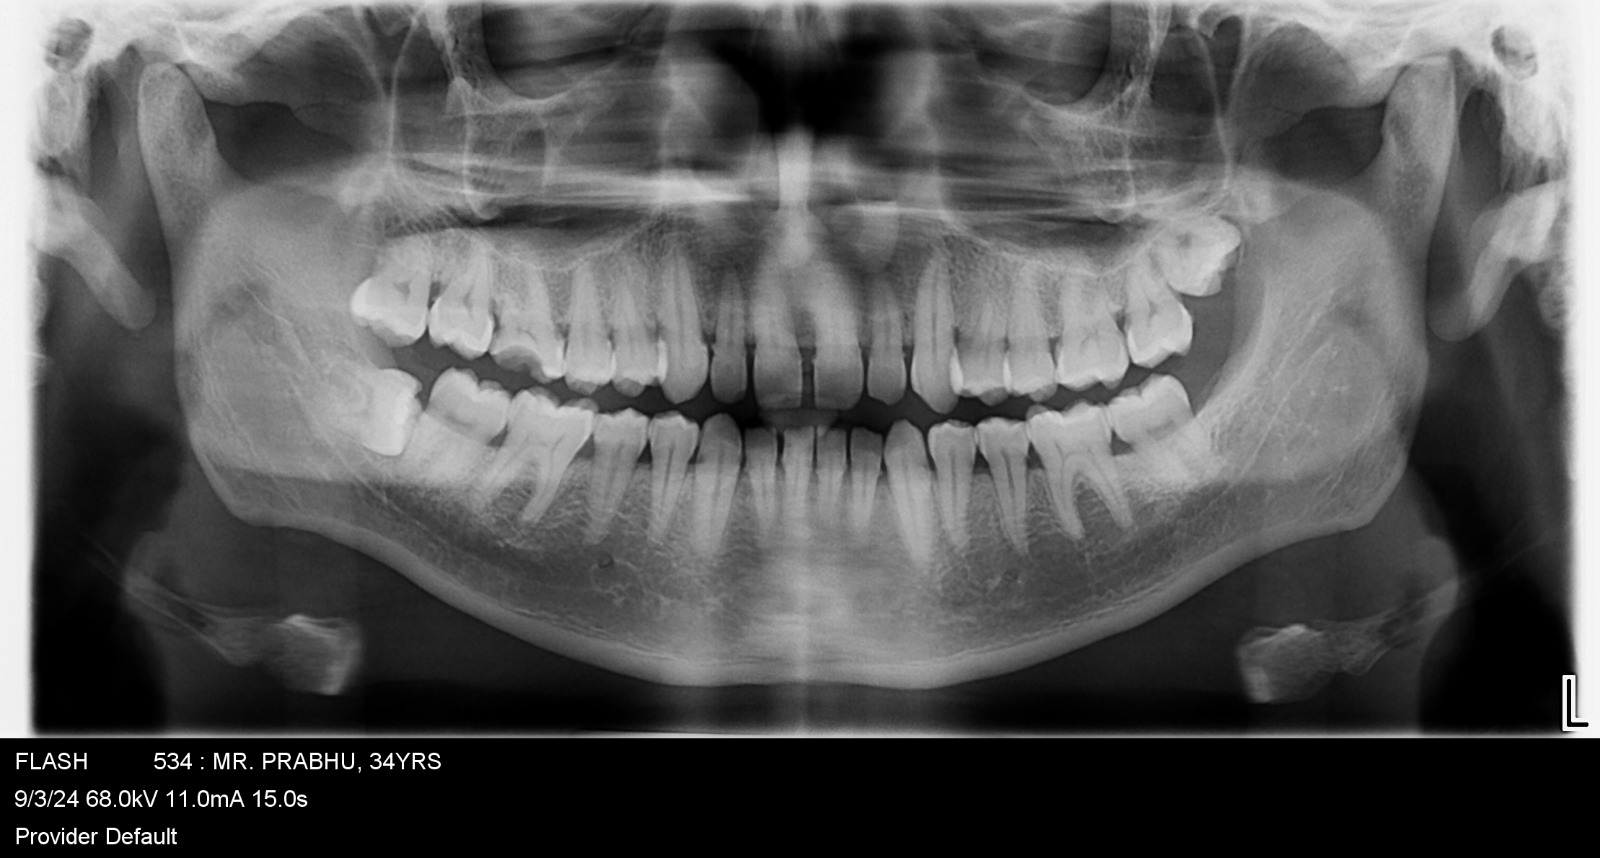

Images Of Dental Treatment Servcies Done At Our Hospital